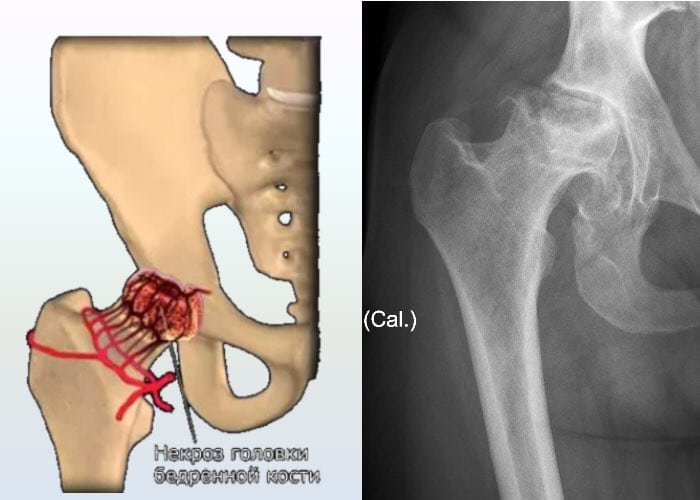

- асептический некроз костной головки — отмирание тканей в тех участках, где на тазобедренный сустав ложится наибольшая нагрузка. Симптоматика патологии проявляется так: на начальном этапе боль в правом или левом бедре резкая, внезапная, локализующаяся в области сустава. Затем она распространяется в пах, пояснично-крестцовый отдел позвоночника, колено. В течение нескольких дней интенсивность болевого синдрома не снижается, мешая человеку не только передвигаться, но и сидеть. Затем самочувствие человека улучшается, дискомфортные ощущения возникают лишь при серьезных физических нагрузках. Вскоре они возвращаются, а их выраженность значительно усиливается.